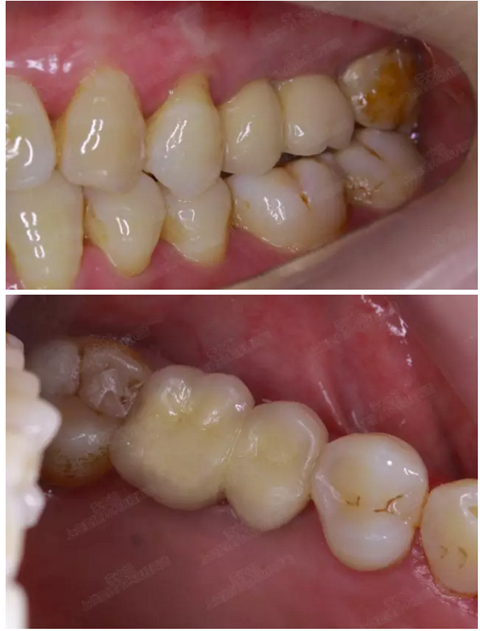

口內(nèi)照片

001.png

修復(fù)后一年

002.png